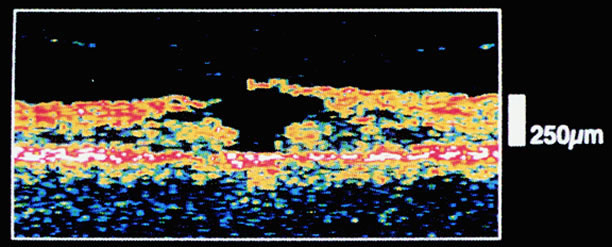

The mechanical relationship between the vitreous and the retina is mediated by the posterior vitreous cortex, which is also called the posterior hyaloid. The posterior vitreous cortex consists of relatively densely packed type II collagen fibrils arranged tangentially to the retina. The retinal basal lamina is the basement membrane of the Müller's cells that comprise the internal limiting membrane (ILM) of the retina.6,7 Ultrastructurally, the ILM consists of three layers.8 Adjacent to the end feet of the Müller's cells is the lamina rara interna. The lamina rara externa is contiguous with the vitreous cortex. In between these layers is the lamina densa. Collagen fibers of cortical vitreous are tangential to the lamina rara externa. The ILM is composed of primarily type IV collagen but also contains fibronectin, laminin, and type I collagen.9 The morphology of the ILM varies topographically in the retina. The ILM, and in particular the lamina densa, is thin in the retinal periphery and becomes increasingly thicker and irregular in the posterior retina.6,8

The ILM thickens from 50 nm at the vitreous base to 300 nm at the equator to 1900 nm posteriorly. In the foveal region the ILM thins to 10 to 20 nm.10

The nature of the adhesion between the vitreous cortex and the ILM is enigmatic. This adhesion is strongest at the optic nerve, the macula, the vitreous base, and retinal vessels. Foos6 demonstrated attachment plaques between Müller's cell cytoplasm and the ILM in the basal and equatorial retina (Fig. 2). Vitreous traction mediated by vitreous fibrils may contribute to these adhesions. These attachment plaques are not present posterior to the equator except where the ILM is thinned in the fovea. This anatomic variation in the fovea region may play a role in the pathogenesis of some of the vitreomacular disorders.